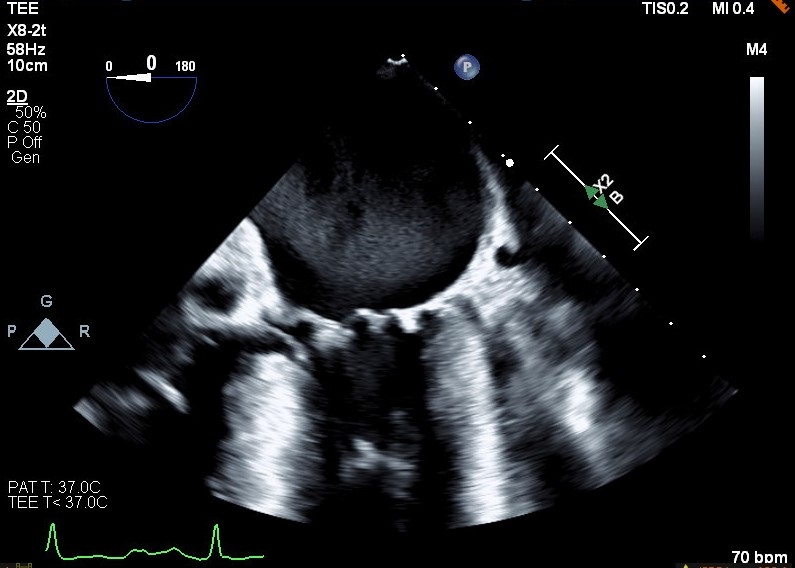

This case demonstrates classic cardiac physiology revealed in an unorthodox manner. Our patient is a 76-year-old male with a past medical history of HOCM, CAD, mild mitral regurgitation who presents to the hospital in the setting of chest pain. Work up revealed a high sensitivity troponin trend concerning for NSTEMI. Patient underwent a left heart cath where he was found to have a proximal LAD lesion with 99% stenosis requiring stenting. Post-intervention patient developed recurrent chest pain and a stat echocardiogram raised concerns for impending cardiogenic shock. Patient thus underwent emergent left and right heart cath. Impella LVAD placed for hemodynamic support. TEE was later obtained revealing moderate to severe mitral regurgitation, representing a progression from prior. At this time both advanced heart failure and structural heart service were consulted. The progression of the patient’s mitral regurgitation was thought to be impacting clinical deterioration and mitral valve transcatheter edge-to-edge repair (TEER) was discussed to address MR in the setting of obstruction. A multidisciplinary meeting resulted in decision to proceed with mitral valve TEER. Baseline hemodynamic gradients confirmed the presence of HOCM with peak-to-peak pressure gradient of 110 mmHg. Intraoperative TEE confirmed the presence of SAM and severe MR. The patient was prepared for a Pascal ACE clip, though in setting of this procedure phenylephrine was required for blood pressure support, revealing improvement in both SAM and MR. The patient was hemodynamically challenged with phenylephrine resulting in temporary resolution of MR and LVOT obstruction. These findings demonstrated a competent mitral valve with regurgitation resulting from HOCM physiology. After a multidisciplinary discussion, decision made to abort and withhold MV TEER.

This case demonstrates classic HOCM physiology in the setting of an attempted TEER procedure. With the addition of phenylephrine and increased afterload SAM resolved, as did much of the patient’s valvular regurgitation. This confirmed a competent mitral valve impacted by HOCM physiology rather than primary mitral valvular pathology. This case demonstrates the impact of structural imaging and competent imagers in the setting of complex anatomy and physiology. In this case TEE findings from provocative hemodynamic testing prevented unnecessary procedures.